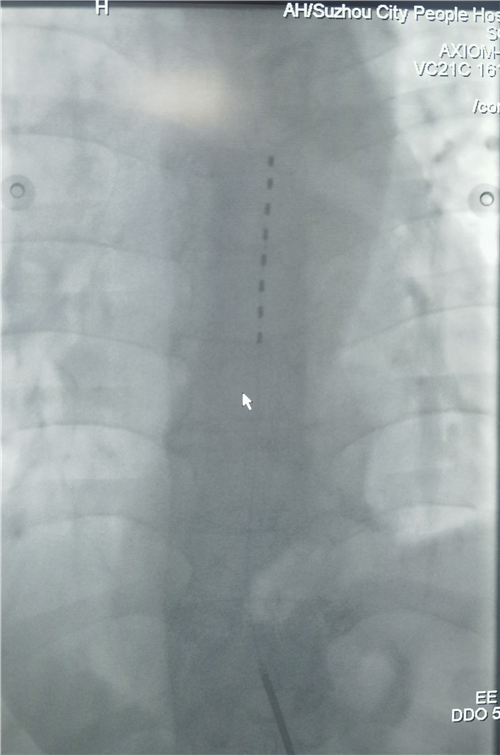

1.微创植入电极:通过微创手术将电极放入椎管硬膜外腔,位置相当于脊髓“信号中转站”;